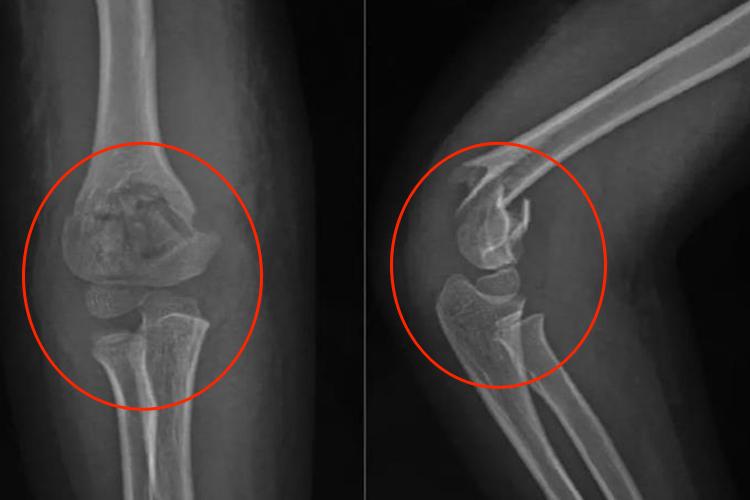

伸直型肱骨髁上骨折的症状根据伤后是否有移位骨折而有所不同。无移位骨折时,肘部肿胀、疼痛,肱骨髁上有明显的压痛、功能障碍,X线可见骨折裂缝;有移位骨折时,肘部肿痛较明显,肿胀严重时可出现张力性水疱,肘后突起呈靴形畸形,但肘后三角关系仍保持正常,X线可见骨折断端移位。